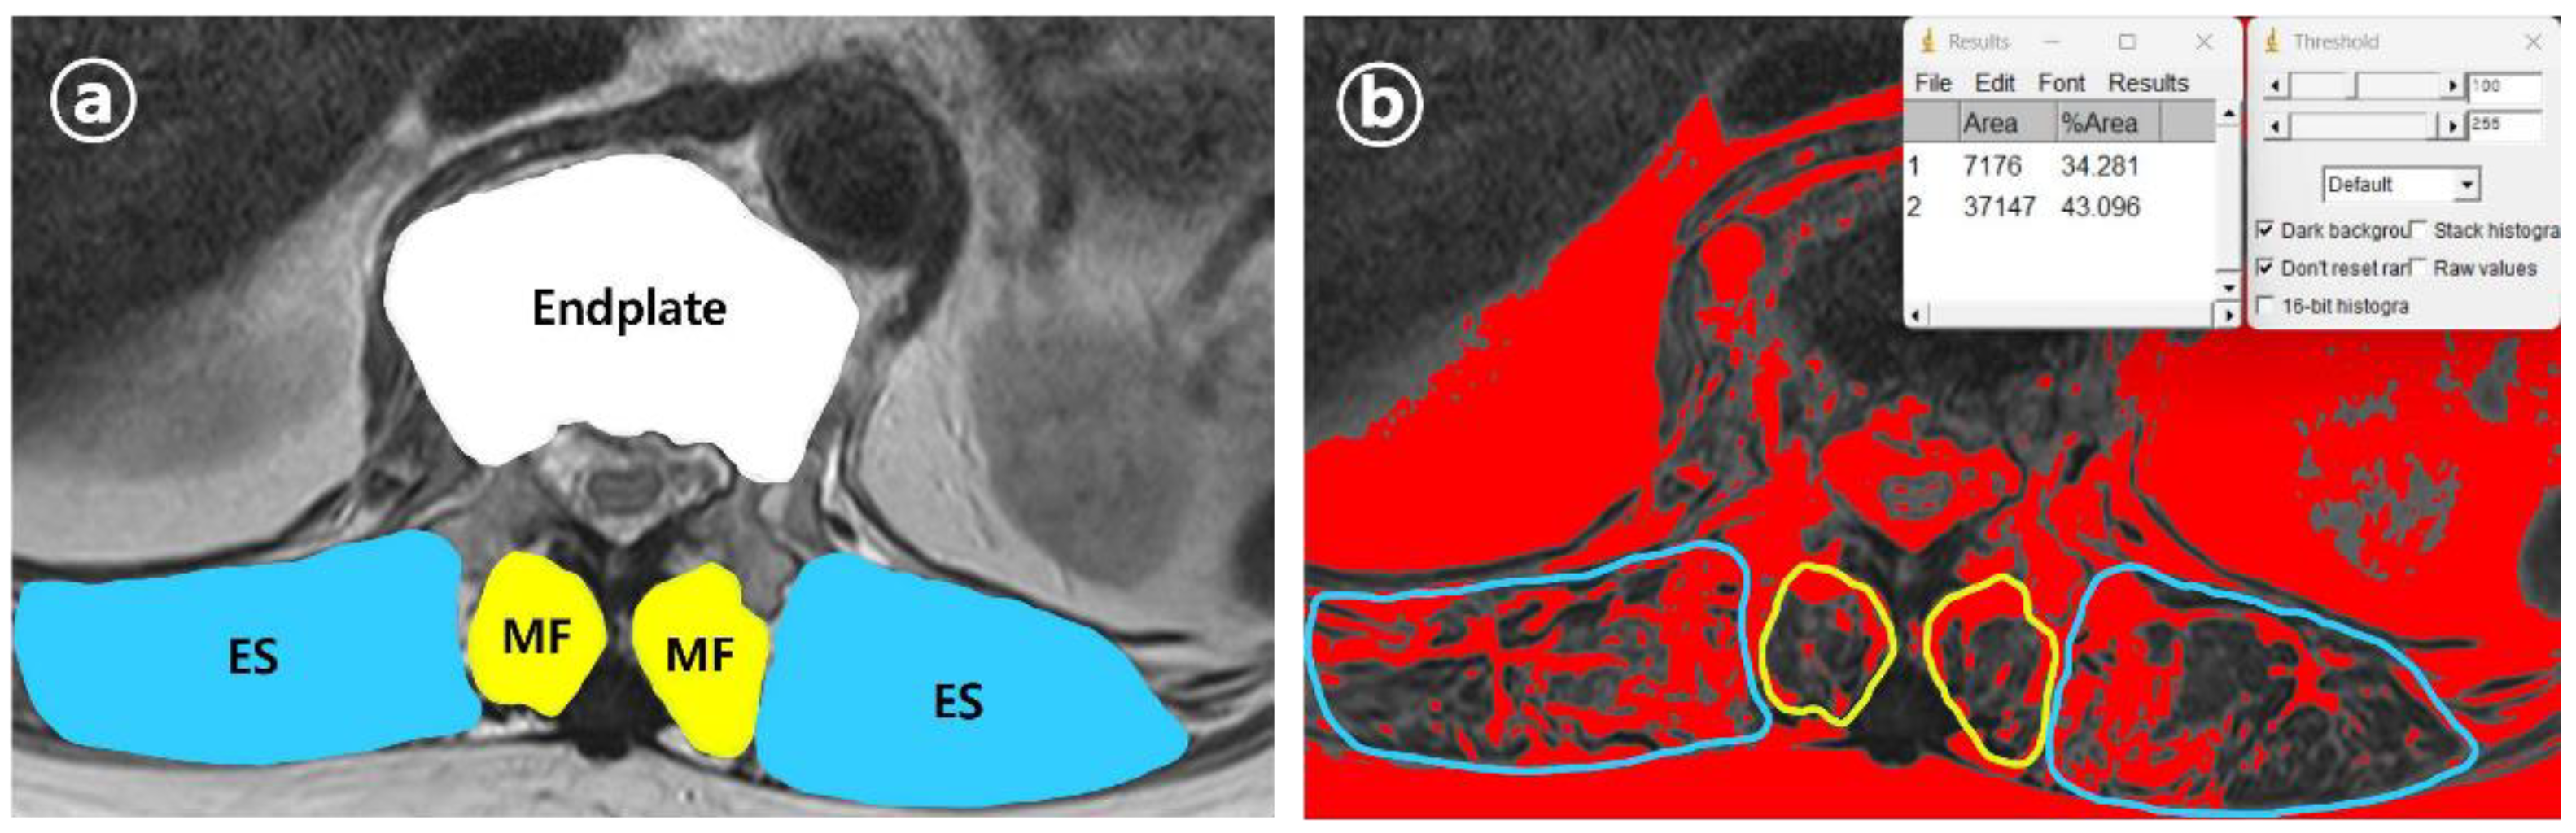

A clinical data warehouse (CDW) containing all medical records from the institution was used to select and study patients. Demographic and radiological data were collected from all enrolled patients. The demographic data included sex, age, diabetes, hypertension, adrenal insufficiency, hyperthyroidism, hypothyroidism, and steroid use. Radiological characteristics were measured using the following variables: the “angle” (local kyphotic angle) and compression ratio of the VCF were measured from the lateral view of the plane radiograph (PR) (Figure 2). From the axial view of MRI, the cross-sectional areas (CSA) of the VCF location and multifidus (MF) and erector spinae (ES) muscles were measured. Additionally, the percentage of fatty infiltration in MF (MFfi) and ES (ESfi) was measured using the imaging pre-processing ImageJ software (version 1.8.0) (Figure 3). In this study, relational multifidus (rMF) was defined as the MF/CSA of the endplate, and relational erector spinae (rES) was defined as the MF/CSA of the endplate.

Figure 3. Measurement variables from axial view, (a) Measurement of CSA of endplate, MF and ES of VCF location, measured within PACS system MRI axial view. The CSA of MF, ES was calculated as the mean of the left and right CSA. (b) MFfi and ESfi measured within ImageJ program and calculated as the mean of the left and right fatty infiltration percentage.